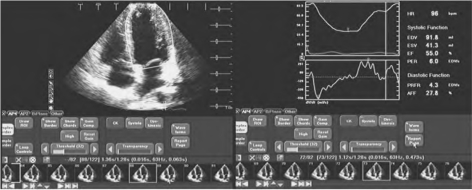

首先受检者平卧位或左侧卧位,连接肢体心电图,分别取胸骨旁左室长轴、左室乳头肌短轴、心尖四腔及二腔等切面,获得清晰的二维图像。在进入AQ设置后,以心电图作时间标志,根据检查目的将感兴趣区(ROI)置于要检查的部位,适当的调节ROI的大小,仪器即可实时自动显示所扫断面的心腔面积时间曲线、容积时间曲线及其变化率曲线(图11-3)。

图11-3 AQ分析图像